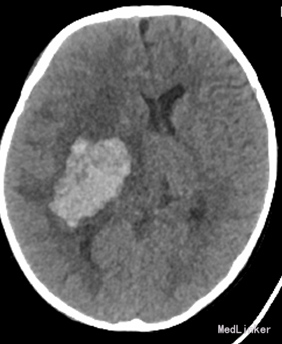

查体:T:36.8℃,P:173次/分,R:30次/分。神志清楚,舌下见约3*2cm水泡,左侧肢体肌力3级,右侧肢体肌力5级。辅助检查:院外CT:右侧基底节区出血。右侧基底节-顶叶区脑出血,大小约5.2cm×3.3cm,周围见大片状水肿带,右侧脑室受压变窄,中线结构左侧移位,环池不对称。CTA示:未见确切异常。全脑血管造影提示:颅内血管未见异常。寄生虫检查示:“猪囊尾蚴IgG阳性,血常规提示缺铁性贫血。

诊断:右侧基底节区顶叶出血,猪囊尾蚴病,缺铁性贫血。给予神经节苷脂钠,甘露醇注射液治疗。